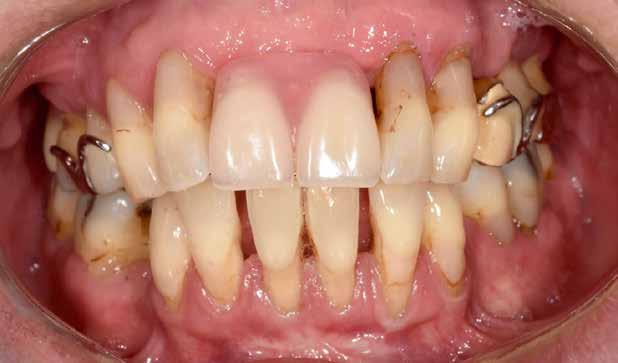

1–2. képek: Kiindulási helyzet.

Kiindulási helyzet

A páciens látlelete a következő:

• krónikus általános parodontitis

• a 24-től terjedő parodontális fekély

• hatástalan kapcsos felső fogpótlás (1-2. képek)